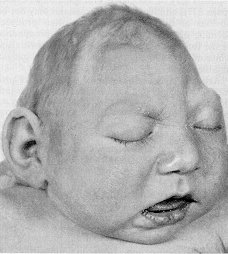

5. Microcephaly

Mikrosefali

adalah kondisi yang sangat langka yang terlihat langsung saat lahir,

dan kadang-kadang bahkan sebelum. Ini mempengaruhi 1 dalam setiap

666.666 di AS Dengan microcephaly, otak tidak dapat berkembang dengan

baik, atau dalam beberapa kasus berhenti untuk tumbuh sama sekali,

sementara bayi masih dalam kandungan. Hal ini menyebabkan kepala lebih

kecil dari kepala bayi normal saat lahir. Banyak yang percaya bahwa

penyakit ini disebabkan oleh paparan zat berbahaya sementara dalam

paparan, rahim untuk radiasi, atau masalah genetik. Penyakit ini

biasanya dipasangkan dengan sindrom Down. Mereka yang memiliki

microcephaly biasanya mental terbelakang dan akan memiliki masalah

dengan hiperaktif, kekerdilan, kejang, masalah keseimbangan, masalah

bicara dan motorik, serta yang lain.